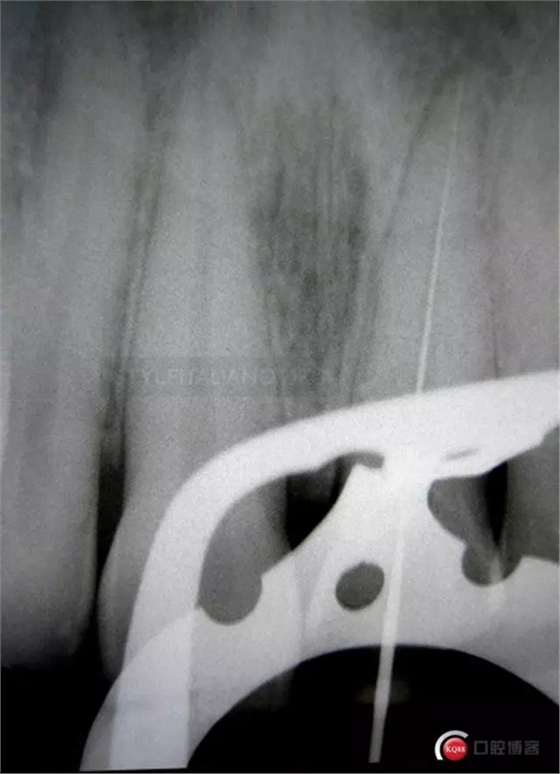

More than 5 mm fracture. Tooth 2.2 is still vital

So, after the root canal treatment under the dam with correct pulp chamber opening, a cleaning of the cavity access and a root filling level control